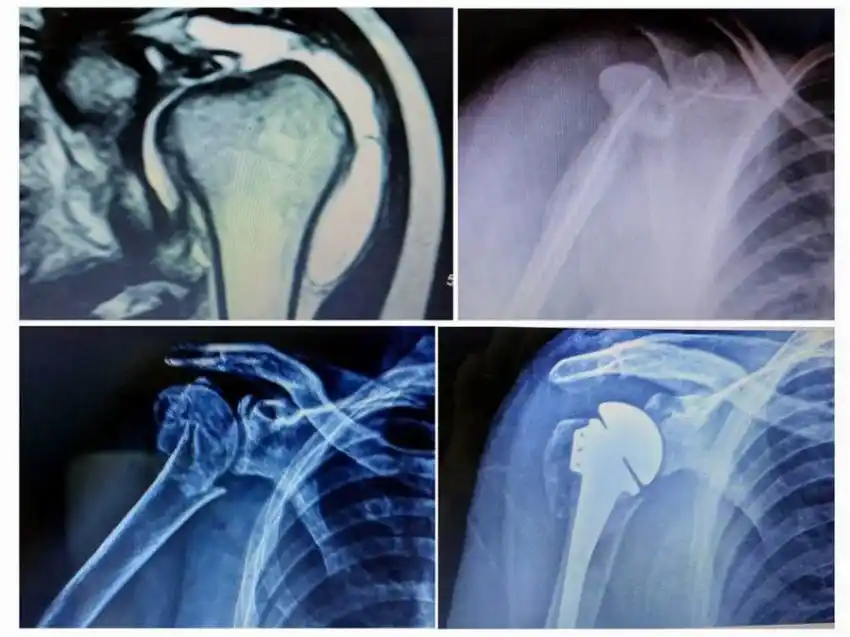

En una cirugía que duró más de tres horas, el equipo del servicio de Traumatología del Hospital de Alta Complejidad realizó por primera vez un implante de prótesis reversa de hombro y logró

entre otras cosas una mejora sustancial en la calidad de vida del paciente que se intervino.

El objetivo principal de poner una prótesis invertida de hombro es la disminución e incluso desaparición del dolor y la mejora funcional (mantener la movilidad previa del brazo, e incluso mejorarla). Está indicada en aquellas personas con un hombro degenerativo, con rotura tendinosa, fractura de húmero en 3 o 4 fragmentos, artritis reumatoide o fallo de otra prótesis.

El Servicio de Traumatología además lleva adelante cirugías como prótesis de hombro convencional y fractura de clavícula, conjuntamente con las prestaciones ambulatorias que brinda. Dicho servicio recientemente fue nombrado por la Asociación Argentina de Cirugía de Hombro y Codo, como centro de referencia de cirugía de hombro.